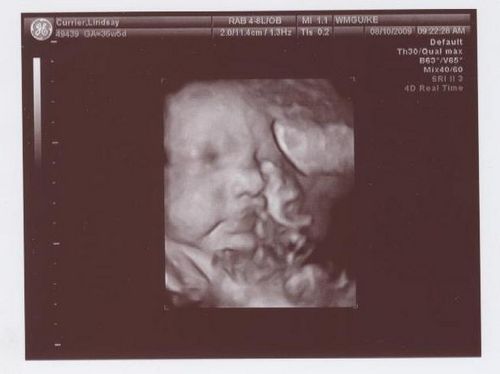

Настала 36 тиждень вагітності, фото показує маленьке диво, яке щаслива мама вже зовсім скоро зможе потримати на руках. До цього моменту у малюка формуються основні рефлекси.

На 36 тижні вагітності фото дитини може бути зроблено в період, коли він не спить і мама зможе розгледіти, що його щоки округлилися і він значно виріс. Всі органи малюка повністю сформувалися, триває розвиток нервової системи і зміцнюються кістки. Обов'язково треба, щоб мама була морально готова до пологів, якщо вагітність багатоплідна або пізня. Тому що в цьому випадку 36 тиждень вагітності, фото якої зроблять в медичному центрі при обстеженні, може стати першим тижнем життя малюка або малюків.